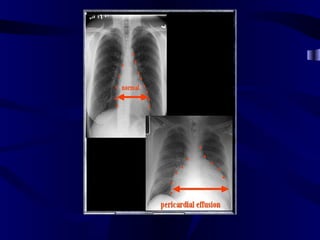

Heart Size • Normal is <50% on PA upright radiograph

Increased Cardiac Size Normal for comparison Cardiomegaly (Big heart)